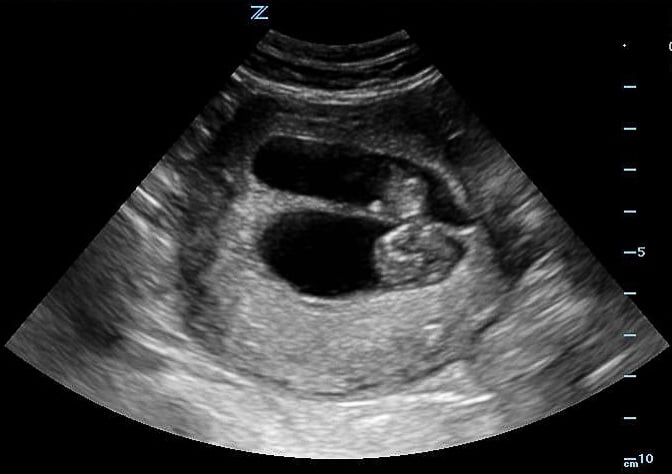

- If the fetal cranium is in the pelvis, then the fetus is vertex.

- Mechanical Risk Factors for Delivery

Figure 29. Transverse suprapubic view revealing the fetal cranium in the pelvis, consistent with a vertex presentation. Note the calipers measuring a bi-parietal diameter at 30 weeks and 6 days.